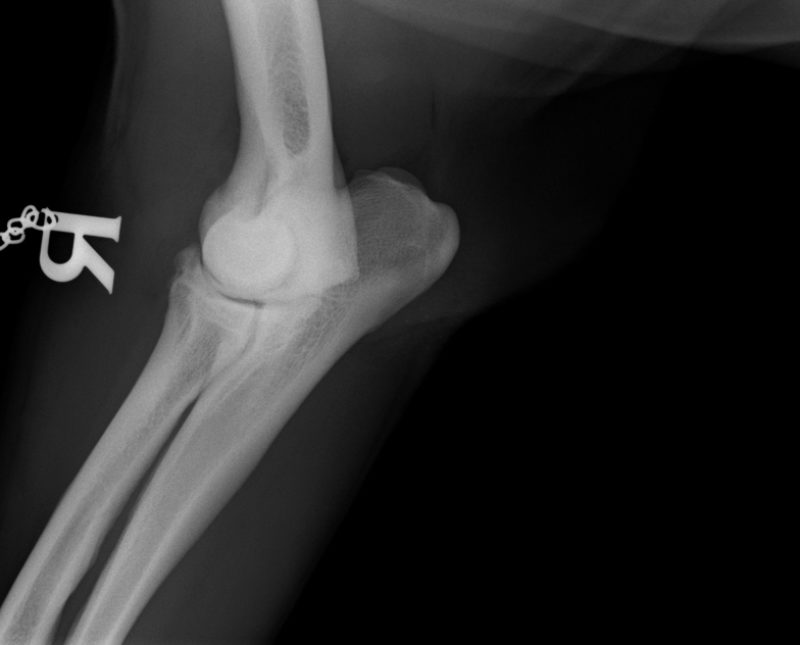

Ellenbogengelenksarthrose bei Labrador ...

Im August 2013 wurde ein acht Jahre alter männlich kastrierter Labrador mit beidseitig hochgradiger  Ellenbogengelenksarthrose vorgestellt. Der Hund war beidseits wegen eines frakturierten Processus Coronoideus (Der Proccesus Coronoideus stellt einen wichtigen knöchernen Stabilisator des Ellenbogengelenks dar) operiert, einseitig nachoperiert und auf beiden Seiten mehrfach mit Cortison-Injektionen behandelt worden.